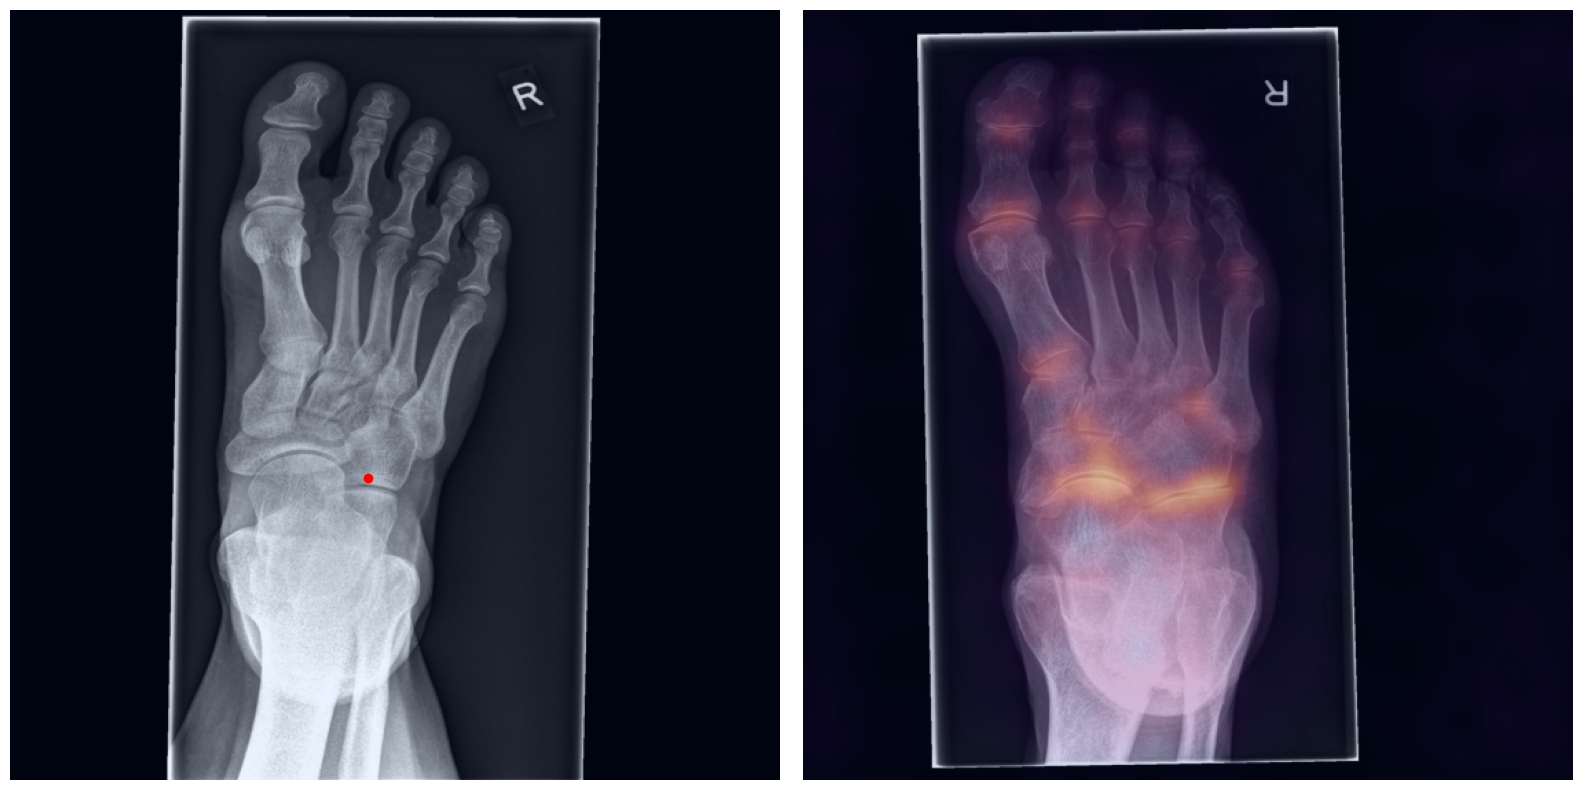

Artificial intelligence (AI) has shown great potential in assisting radiologists with musculoskeletal (MSK) assessments across various anatomical regions1,2,3,4. However, most existing tools are narrowly tailored for specific anatomies or rely on segmentation-based methods as a basis. To address these limitations, we propose a versatile and generalist AI-based approach for landmarks matching. In contrast to typical generalist landmark matching approaches that depend on automatically identified, optimally descriptive landmarks5,6,7, our use-case has to be based on manually selected landmarks tailored for MSK measurements. As these landmarks are potentially subotimal for precise matching, we employ an AI-based method8 that first performs multi-scale dense image matching between the reference and target images independently of the landmarks. The AI uses a combination of transformer and convolutional neural networks to establish a multi-resolution descriptive feature representation of each position within the images, allowing to define correspondences between the reference and target images. In a subsequent step, landmark positions are transferred to the target image based on these correspondences, with the determination of final locations benefiting from the redundancy of the dense matching. This enables robust automation of landmark matching from a reference patient across an entire cohort of target patients. The approach is anatomy-agnostic, enabling the use of the same backbone model for a wide range of anatomical regions and MSK measurements. For more detailed information we refer to our paper.

Once a correspondence between the reference and target radiographs is established, landmark matching can be performed in real-time. This process enables the alignment of individual points and allows for the definition of a predefined set of landmarks that can be mapped onto the target patient. These predefined landmarks can be customized for the automated calculation of specific measurements, which, once defined on a reference patient, can be consistently and automatically transferred to any radiograph within the target cohort.

The process of establishing a dense match between two images relies on abstract feature representations for each position in both the reference and target images. To better understand which information is encoded by the AI, we examined the feature similarities between a specific position within the reference image and the entire target image. Our findings show that the AI captures both semantic and texture features. The matching process utilizes this encoded information, along with precise positional data, to create a reliable mapping between the images.